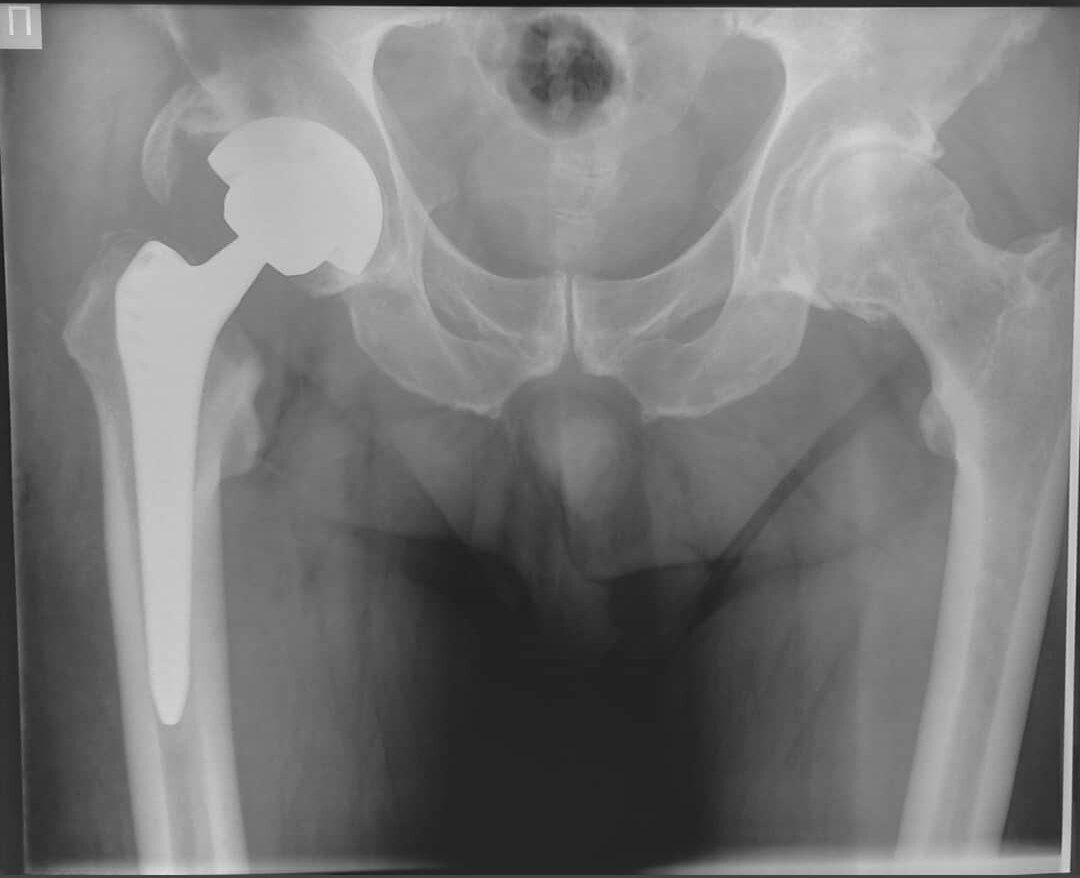

Коксартроз тазобедренного сустава можно лечить консервативно (контроль массы тела, занятие ЛФК, плавание в бассейне и др.). К эндопротезированию приводит ухудшение качества жизни (частые обострения, боль и тугоподвижность мешают работать) и безоперационные методы лечения не помогают.